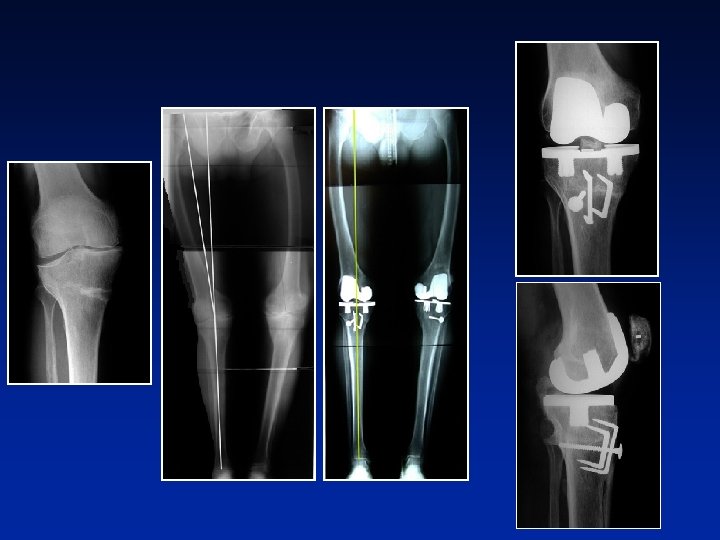

DEFORMITY 206° INDICATIONS = Wear + laxity + Extra-articular deformity 188° Stress radiography allows precise measurements of ligamentous and bony deformities Valgus stress Varus stress

INDICATIONS DEFORMITY 206° = Wear + laxity + Extra-articular deformity 188° Stress radiography allows precise measurements of ligamentous and bony deformities Valgus stress Varus stress

INDICATIONS DEFORMITY = Wear + laxity + Extra-articular deformity

INDICATIONS DEFORMITY = Wear + laxity • Valgus def. = 17°± 10 • Varus def. = 22° ± + ( 9 to 30°) 9 (12 to 34°) Mean deformity in the serie Extra-articular deformity

INDICATIONS DEFORMITY = Wear + laxity • Valgus def. = 17°± 10 • Varus def. = 22° ± + ( 9 to 30°) 9 (12 to 34°) Minimum deformity for indication ? ? Extra-articular deformity 14. 3° 16. 4° 5 -7° ? ?